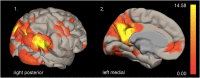

Results: A spatial pattern consistent with the default mode network (DMN) could be identified by independent component analysis. DMN activity was enhanced in APOE4 carriers and related to cortical iron burden. APOE4 and cortical iron synergistically interacted with DMN activity. Secondary analysis revealed a positive, APOE4 associated, relationship between cortical iron and DMN connectivity.